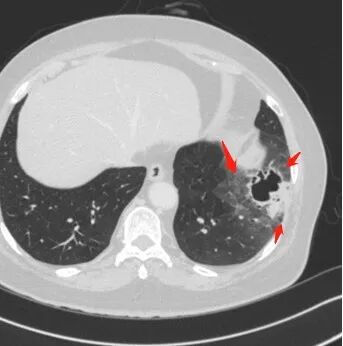

左肺下叶不规则空洞,周围边界清楚磨玻璃影,空洞内可见丝状物及壁结节,空洞壁薄,真菌感染和肿瘤难以分别,倾向感染

女性,65岁,左肺下叶空腔边缘见不规则结节,结节强化轻、不均匀,局部坏死边界较清楚,胸膜为糊墙为主,膈面胸膜判断不清楚似有结节;空腔内见分隔,或者数个融合,局部张力稍弱,边缘见支气管截断和血管集束;外周见大片磨玻璃影,部分边界模糊。结合病史炎症肯定有,但是囊腔结节这部分感觉恶性征象多过良性,考虑囊腔型腺癌可能性大,鉴别肺大疱感染

左肺下叶外侧基底段空洞,壁增厚,轻度强化,周围磨玻璃影,边界清晰,考虑囊腔型肺癌。

左肺下叶见薄壁囊腔影,周围呈磨玻璃样改变,囊腔形态欠规整,囊壁见小结节影,考虑感染性病变,除外囊腔型腺癌。

左肺下叶囊性空腔影,内分隔,壁不均匀,周围磨玻璃边界清楚,胸膜牵拉。倾向腺,鉴别真菌感染。

老年女性,咳嗽、咳痰2月余,CT提示:左肺下叶可见一不规则结节,周边可见磨玻璃密度,边界清,内可见囊腔样改变,内可见分割,内壁不规则,部分可见分叶,引流支气管狭窄,走形僵直,轻度强化,考虑囊腔型腺癌,鉴别曲霉、结核等

老年女性,受凉后咳嗽咳痰发热两天,近两天咳嗽加重。CT示左肺下叶不规则空洞伴局部洞壁结节,空洞内见分隔,似见扩张支气管相通。空洞周边伴大片磨玻璃影。结节与胸膜宽基底相连,轻度强化,考虑为囊腔型腺癌伴感染

左肺下叶空洞结节,薄壁,局部可见壁结节,支气管于边缘走形中断,周围磨玻璃影,边界不清。先考虑感染,鉴别囊腔腺癌。

老年女性,左下肺病灶,空洞,璧厚薄不均,内有壁结节,周围磨玻璃,边界清,符合假大空,考虑腺癌。

患者老年女性,受凉后咳嗽,咳痰,发热,左肺下叶不规则空洞结节,周围大片磨玻璃影,倾向恶性。

这个病例,老年女性,边缘磨玻璃,中间假大空,磨玻璃边界清楚,腺癌

假大空,壁结节,磨玻璃影=腺癌

右肺下叶假大空,内可见分隔,壁不规则,周围大片磨玻璃影,部分边缘模糊,胸膜受累增厚,肝脏多发囊肿,考虑囊腔型腺癌。

老年人,左肺下叶囊性病变+实性结节+磨玻璃影,尽管病灶相邻胸膜反应较广泛,但是上述影像表现及临床症状,首先考虑肺癌(腺癌),相邻胸膜反应广泛有可能为肺癌合并感染性病变所致。

女性,65岁,咳嗽、咳痰2月余,伴发热数日。

胸CT:左肺下叶囊腔,壁厚薄不均,可见壁结节,囊腔内可见断裂小梁,部分融合,周围边界较清楚GGO,胸膜牵拉,可见血管集束、支气管充气征,冠状位部分层面可见支气管在囊腔边缘截断。考虑:囊腔型腺Ca。鉴别:肺大疱感染,CPAM等。

1、左肺下叶外基底段不规则囊腔样病灶,囊腔内有条形影及血管穿行。

2、囊壁薄厚不均匀,稍显僵硬,有壁结节(对应边缘分叶等)、结节强化明显。

以上两条几乎将肺囊肿彻底排除在外,且高度怀疑新生物!

3、灶周环以大范围磨玻璃影,非常均匀,没有重力分布趋势,分叶状,边界隐约可变。

4、冠状位部分层面可见支气管在囊腔边缘截断。